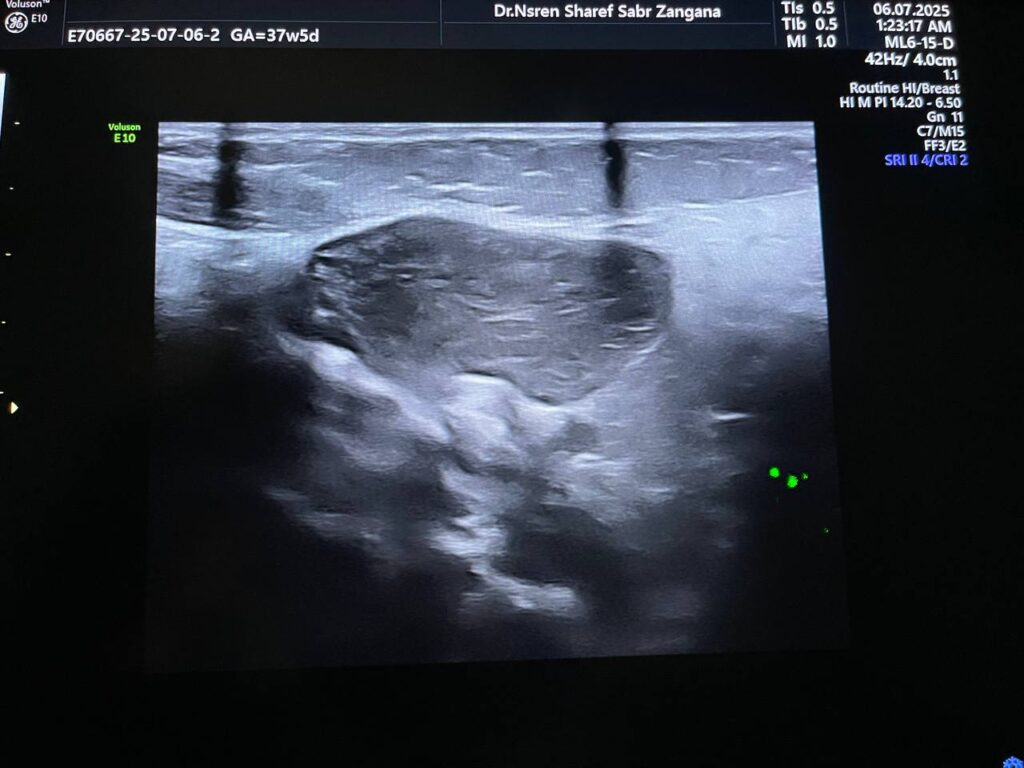

Presence of circumscribed soft solid mass, its size 26x14x27mm , inferior to the left sternocleidomastoid muscle , its vascular on color Doppler , could be ectopic thymus gland ?, others ? further study to exclude other pathology

Normal thyroid gland

No pathological lymph node seen